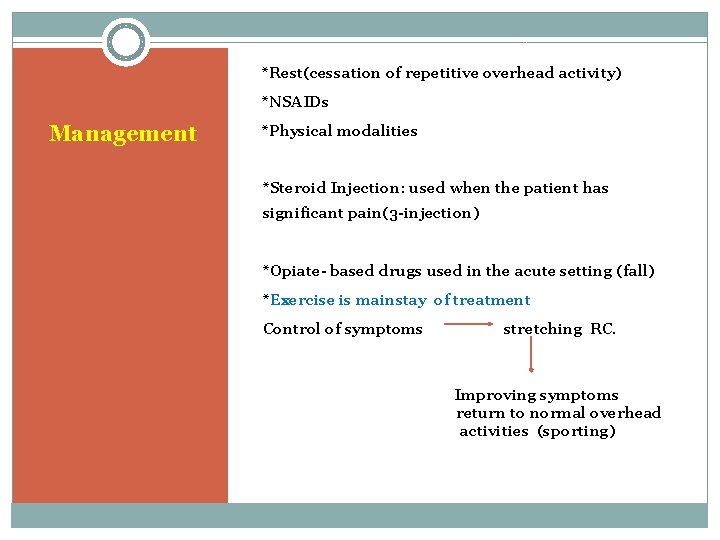

*Rest(cessation of repetitive overhead activity) *NSAIDs Management *Physical modalities *Steroid Injection: used when the patient has significant pain(3 -injection) *Opiate- based drugs used in the acute setting (fall) *Exercise is mainstay of treatment Control of symptoms stretching RC. Improving symptoms return to normal overhead activities (sporting)